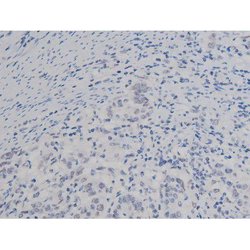

Antibody detects endogenous levels of Nucleophosmin only when phosphorylated at Threonine 199.

| Applications | Immunohistochemistry (Paraffin), Western Blot, Immunocytochemistry |